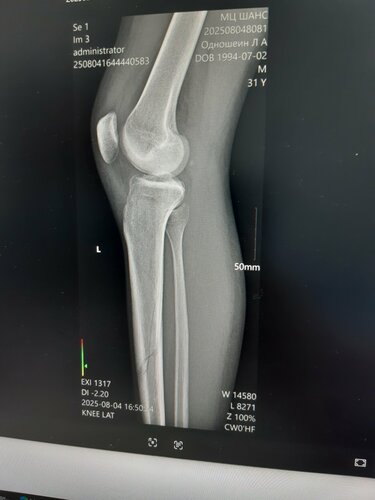

Добрый день. Припереломе Большой берцовой кости, максимум что смогла сделать эта больница это откочать кровь из сустава и наложить гипс. Снимков они не предоставили, как бы я не умолял (говорили нам некогда тебе анотомию преподавать, ты там всёравно ничего не поймёшь). В итоге после снятия гибса у этих же "врачей", разумеется опять без предоставления снимков на руки ( показали только на собственном телефоне), не давая никокого заключения сказали можешь идти от перелома и следа не осталось, как в дальнейшем выесниться они даже не в том месте снимок сделали. Через неделю я начал беспокоиться что не могу согнуть ногу и обратился в клиннику "Шанс", где мне сделали снимок, скинули его на диск, всё "разжували", чтобы я понял, и оказалось мне и гипс то рано сняли и на ногу вообще ещё рано втавать, а в 14 - й больнице сказали всё зажило можеш полностью вставать но ногу. Что касается общения с больными, судите сами. В первый день обращения, мне стали откачивать кровь из колена (я им только за это блогадарен сделали всё хорошо), но так как у меня вес тела всего 52 кг, а крови откачали много 100 мл.(относительно моего веса), мне сделалось плохо, в глазах потемнело и в этот момент они меня стали прогонять (давай быстрее у нас времени мало), я лежал не уходил (да и не смог бы если бы даже захотел, у меня нижняя половина туловища почемуто отказала полностью), они снапором меня стали прогонять, в это время я стал писать другу по ватсапу , который меня ждал в коридоре, с просьбой заступиться за меня, славо богу успел написать, потомучто у меня стали отбирать телефон (прямо силой из рук вырывать), когда друг зашёл они успокоились. На фотографиях видно с каким переломом меня выпустили из 14 -й больници и сказали что от перелома и следа не осталось, можеш идти.